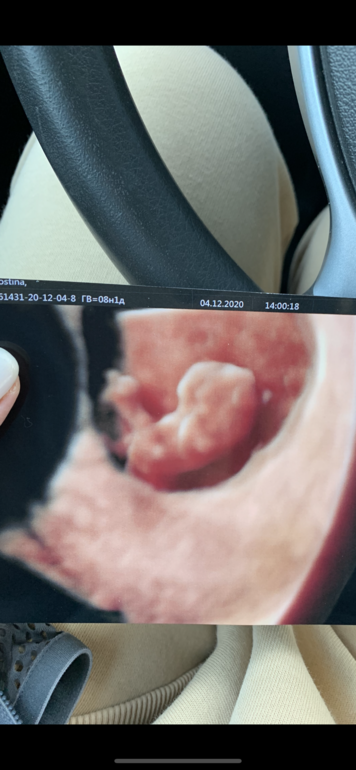

Сделал мне наши первую фотку ❤️

О, какая классная 3D фотография!!!

По размзи вроде мальчик - прикрепление сверху слева.